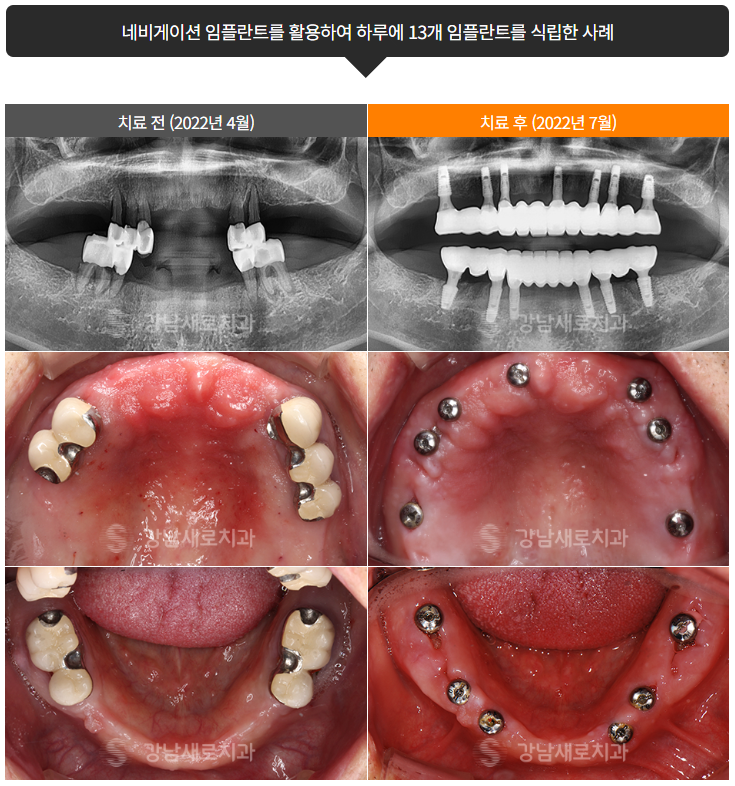

네비게이션 임플란트

임플란트수술이 꺼려지는 원인이 임플란트붓기 임플란트출혈 임플란트통증 이라면 생각해볼 수 있는 방안은 네비게이션 임플란트입니다. 이는 임플란트수술 전 미리 식립 예상 경로를 예측하여 가이드를 제작해 임플란트수술을 하는 것으로, 각 개개인에 따라 다른 치열과 잇몸 상태, 뼈 구조 등에 맞춰 가능한 가장 올바른 식립 위치와 방향을 미리 두기 때문에 임플란트붓기 임플란트출혈 임플란트통증 을 최소화할 수 있게 됩니다.

네비게이션 임플란트란 3D 디지털 모델링으로 가상 현실 기술을 활용하여 수술 전에 시뮬레이션을 진행하므로 개개인에 따라 다른 식립 위치 및 방향의 치료 계획을 올바르게 파악, 설정하여 임플란트붓기 임플란트출혈 임플란트통증 을 비롯한 부작용을 최소화한 수술 과정과 결과를 보입니다.